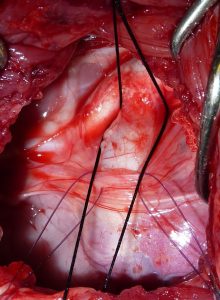

Portosystemic Shunts in Small Animals

Portosystemic Shunts in Small Animals at Eastcott Referrals About Portosystemic Shunts in Dogs & Cats Portosystemic Shunts (PSS) are ...